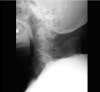

AP & lateral X-ray 촬영을 하면 척추종판(end plate)에서 반응성 골변화로 인해 골편이 전방으로 돌출, 후관절에서 생긴 골편이 신경구멍 방향으로 탈출, 추체의 후방에서 생긴 골편이 척추관으로 돌출되어 협착을 유발한 것 등을 관찰할 수 있습니다. 추체 하나가 인접한 추체에 비해 전방으로 아탈구되었다만 협착증 가능성이 커집니다. 이러한 퇴행성 변화는 C56, C67 디스크 공간에서 가장 호발합니다.